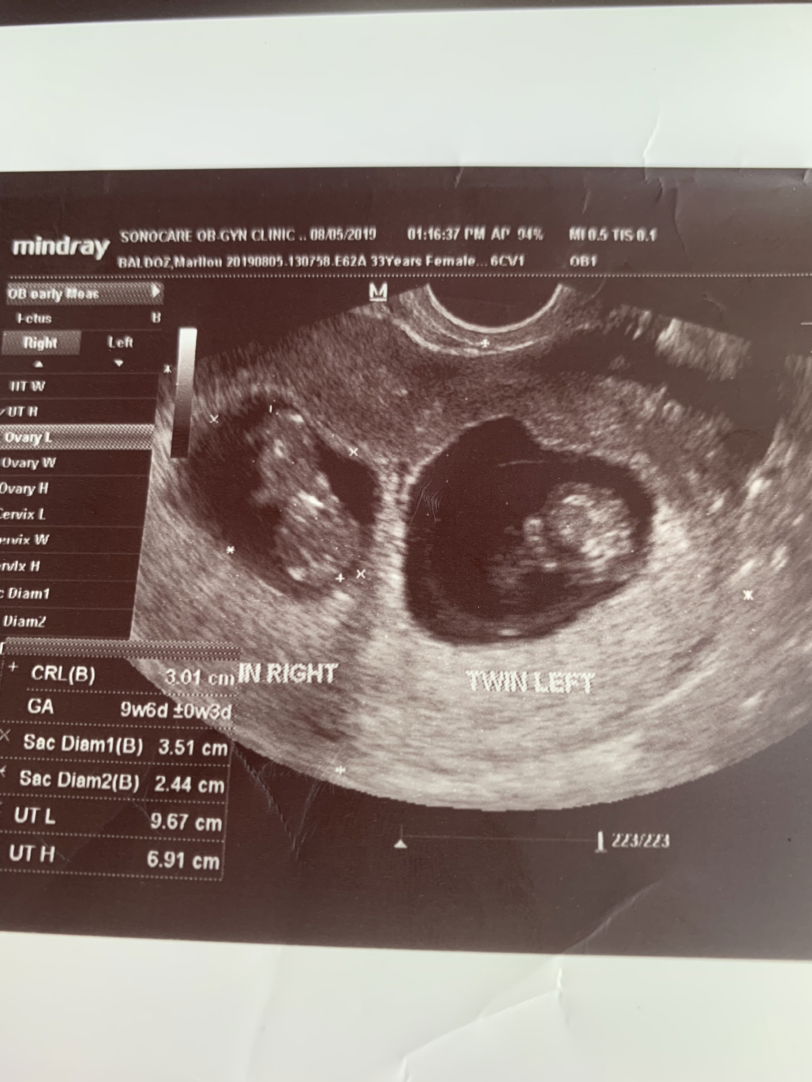

Hoping for a child

Twins